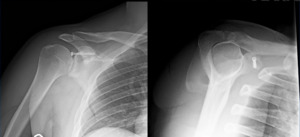

Imaging: Preoperative imaging included standard radiography using anteroposterior, Grashey, scapular Y and axillary views (Fig 1-2). After determining the presence of a coracoid fracture, advanced imaging was conducted via computed tomography with addition of 3-dimensional reconstruction. CT imaging was suggestive of a type 2 coracoid fracture nonunion (Fig 3) which was then further verified with no enhancement with T2 MRI sequences (Fig 4).